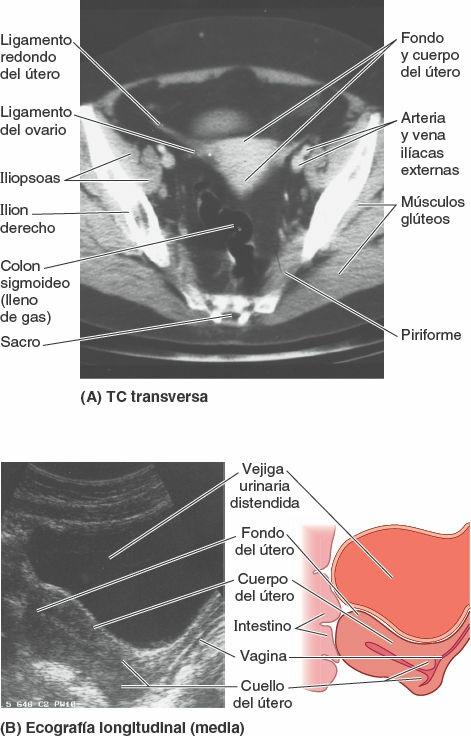

Útero

El útero (matriz) es un órgano muscular hueco, con paredes gruesas y forma de pera. El embrión y el feto se desarrollan en el útero. Sus paredes musculares se adaptan al crecimiento del feto y posteriormente proporcionan la fuerza necesaria para su expulsión durante el parto. El útero no gestante (no grávido) se sitúa generalmente en la pelvis menor, con el cuerpo apoyado sobre la vejiga urinaria y su cuello entre esta y el recto (fig. 6-43 A).

El útero adulto suele estar en anteversión (apuntado anterosuperiormente respecto al eje de la vagina) y anteflexión (el cuerpo del útero está flexionado o inclinado anteriormente, en relación con el cuello del útero, creando el ángulo de flexión), de manera que su masa se sitúa sobre la vejiga urinaria. Por lo tanto, cuando la vejiga urinaria está vacía, el útero se sitúa típicamente en un plano casi transversal (figs. 6-43 A y B, y 6-44 A). La posición del útero varía con el grado de repleción de la vejiga urinaria (fig. 6-44 B) y el recto. Aunque su tamaño varía considerablemente, el útero no gestante suele medir 7,5 cm de largo, 5 cm de ancho y 2 cm de fondo, y pesa aproximadamente 90 g. El útero puede dividirse en dos porciones principales (fig. 6-43 B): el cuerpo y el cuello.

El cuerpo del útero, que forma los dos tercios superiores de la estructura, incluye el fondo del útero, la parte redondeada del cuerpo que se sitúa superior a los orificios uterinos de las tubas uterinas (fig. 6-39 B). El cuerpo del útero se sitúa entre las capas del ligamento ancho y puede moverse libremente (fig. 6-39 A). Tiene dos caras: vesical (relacionada con la vejiga) e intestinal. El cuerpo está separado del cuello por el istmo del útero, la región relativamente constreñida del cuerpo (alrededor de 1 cm de longitud) (figs. 6-39 A y B, y 6-43 B).

El cuello del útero es el tercio inferior, estrecho y cilíndrico, del útero, con una longitud de aproximadamente 2,5 cm en la mujer adulta no gestante. A efectos descriptivos se divide en dos porciones: una porción supravaginal, entre el istmo y la vagina, y una porción vaginal, que protruye en la vagina (fig. 6-43 B) y rodea el orificio (externo) del útero, siendo a su vez rodeada por un estrecho receso, el fórnix de la vagina (fig. 6-43 C). La porción supravaginal del cuello está separada de la vejiga urinaria, anteriormente, por tejido conectivo laxo, y del recto, posteriormente, por el fondo de saco rectouterino (fig. 6-43 A).